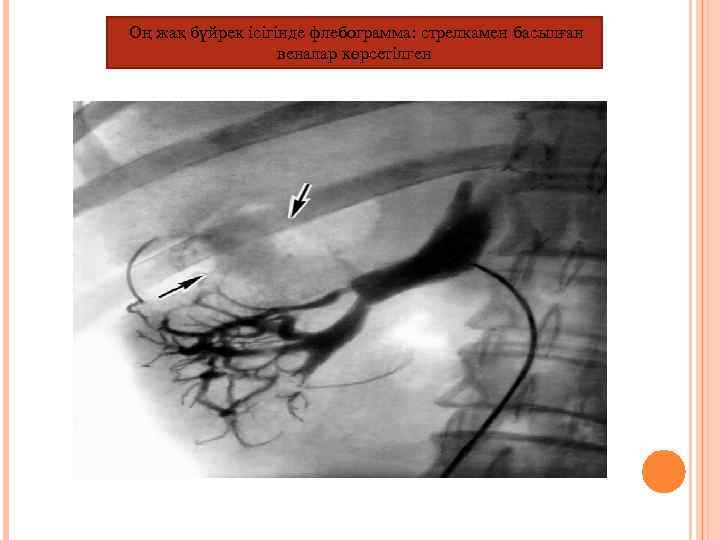

Оң жақ бүйрек ісігінде флебограмма: стрелкамен басылған веналар көрсетілген